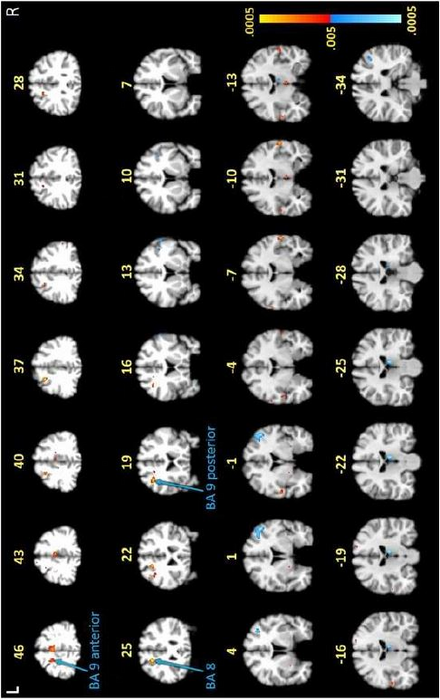

The imaging tests revealed unusual activity in the frontal lobe, an area of the brain responsible for cognitive tasks such as memory recall and concentration. Participants were asked to memorize and recall capital and lowercase letters, as well as the alphabetical order of multiple letters.

Notably, the researchers say, the images showed differences in their frontal lobe activity between the two groups in the white matter of the brain, which normally does not show up in fMRI scans, as this tissue operates with less blood flow than gray matter. White matter is crucial for moving information around the brain, acting like train tracks that help deliver information to the train depot, or gray matter.

“We saw certain areas in the frontal lobe under-activating and others that were over-activating, which was somewhat expected,” says Marvel, an associate professor of neurology. “However, we didn’t see this same white matter activity in the group without post-treatment Lyme.”

To confirm this finding, researchers used a second form of imaging called diffusion tensor imaging (DTI) on all 12 participants with Lyme and 12 of the 18 non-Lyme participants. DTI detects the direction of water movement within brain tissue. This unique approach corroborated their fMRI findings and revealed new findings: Water was diffusing, or leaking, along the patients’ axons — the extensions of neurons that carry electrical signals to other neurons — within the same white matter regions identified in the fMRI.